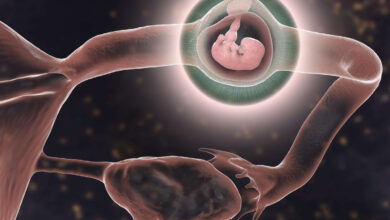

بارداری خارج از رحم

بارداری خارج از رحم، که به طور علمی به عنوان “حاملگی خارج از رحم” نیز شناخته میشود، وقوع بارداری در…

ایا سونوگرافی بارداری خارج از رحم را نشان می دهد؟

سنوگرافی بارداری (PREGNANCY ULTRASOUND) یک فرایند تصویربرداری است که با استفاده از امواج صوتی (ultrasound) برای تصویربرداری ناحیه رحم و…